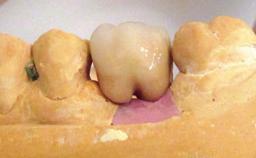

A 47-year-old woman who had suffered from aggressive periodontitis requiring a number of periodontal interventions over more than 10 years was referred by her general dental practitioner and periodontologist for bone augmentation and implant therapy. Her failing dentition had already been scheduled for extraction. The patient expressed a desire for implant-supported fixed restorations and esthetic improvement of her lower face. She had agreed to consult with a maxillofacial surgeon after the referring dentist had suggested bone augmentation. An initial examination by the maxillofacial surgeon revealed mobility of all residual teeth in a patient who was very unhappy with the function of her removable partial dentures. Due to periodontally migrated flaring teeth and loss of occlusal support, the vertical dimension of occlusion was dramatically reduced. The patient was displeased with her lower face because of deepened nasolabial, commissural, and supramental folds.